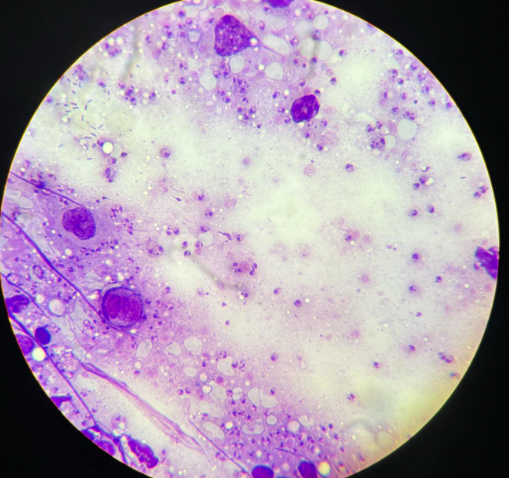

echinococcus granulosus protoskoleksy